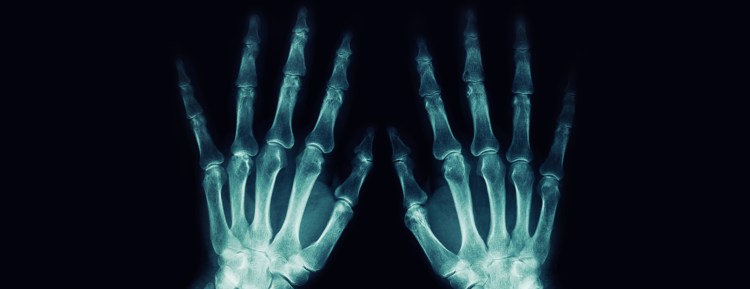

¿Son peligrosas las radiografías?

Hand x-rayEstamos naturalmente expuestos a la radiación todos los días a través del medio ambiente: el sol, las estrellas, el aire y la tierra son fuentes de radiación.

Los altos niveles de radiación pueden dañar sus células, lo que podría provocar problemas de salud como el cáncer. Sin embargo, como los rayos X tienen una radiación relativamente baja, los riesgos asociados son mínimos.

El nivel de radiación de una radiografía depende de la parte del cuerpo que se escanea. Una radiografía de tórax tiene aproximadamente el mismo nivel de radiación que 2, 4 días de radiación ambiental. Una tomografía computarizada puede tener hasta 200 veces más radiación. Hable con su médico acerca de si los riesgos superan los beneficios.

La primera radiografía, de la mano de una mujer joven, se tomó en 1895. Fue un gran avance en la medicina, pero sometió al paciente a una dosis de radiación 1500 veces mayor que la de los rayos X actuales.